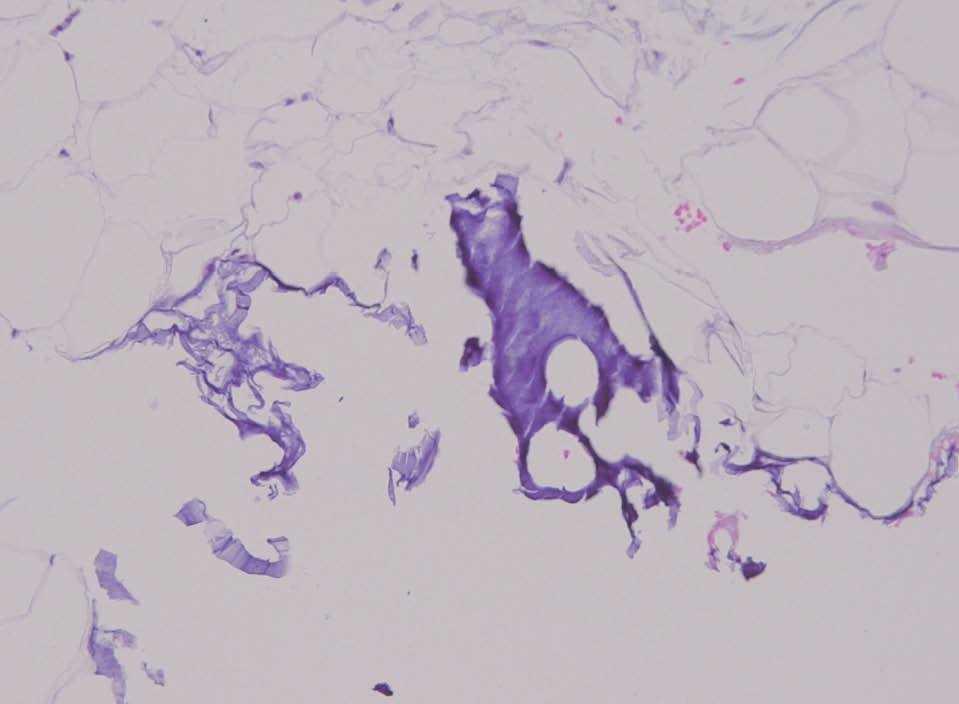

Una mujer de 34 años, sin antecedentes personales de interés ni alergias, recibió inyecciones de Bio-Alcamid® en marzo de 2003 por cicatrices post-acné en ambas mejillas. Desde julio del 2004 presentaba lesiones nodulares, de diversos tamaños con molestias. Una lesión supuró material pastoso con febrícula por lo que tomó claritromicina y urbasón intramuscular con mejoría. Fue vista en consulta en octubre de 2004 (fig. 1) por dichas lesiones nodulares, realizándose una biopsia con abordaje mucoso para no dejar cicatriz. Dicha biopsia no fue lo suficientemente profunda y no mostró alteraciones significativas rechazando la paciente la repetición de la misma. En junio del 2005 la paciente acudió a Urgencias con un nódulo inflamatorio muy doloroso, junto a la comisura bucal izquierda, con febrícula. Fue drenado extrayéndose gran cantidad de material purulento, con gran disminución del tamaño y con muchas menos molestias, pautándose amoxicilina-clavulánico 875 mg/8 horas. Debido a la persistencia de la inflamación se drenó de nuevo tres días después con buena evolución. El producto de este drenaje se mandó a cultivar creciendo un Streptococcus grupo viridans. Asimismo, se realizó una extensión (citología) donde se objetivó una reacción inflamatoria granulomatosa junto con un material extraño (fig. 2). Posteriormente se centrifugó el material restante y el residuo se procesó y tiñó con hematoxilina-eosina obteniéndose un bloque celular. Aquí se objetivó una intensa reacción inflamatoria, con numerosos leucocitos y hematíes, células epitelioides y gigantes junto con un material extraño (figs. 3 y 4).

Figura 3. Bloque celular mostrando reacción inflamatoria, hematíes y material extraño de bordes netos con contorno poligonal (hematoxilina-eosina, x10).

Figura 4. Aproximación del anterior donde se aprecia la sustancia de relleno (hematoxilina-eosina, x200).